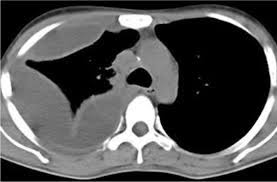

Ultrasound findings are relevant for pleural infection as in heavily septated or loculated effusions, the biochemical results can be different in the discrete areas, so can give falsely reassuring results. Malignant pleural effusion, lymphangitis carcinomatosa: In patients with symptomatic malignant pleural effusions with nonexpandable lung, failed pleurodesis, or loculated effusion, we suggest the use of ipcs over chemical pleurodesis. Rather than layering laterally and blunting of the costophrenic angle, the pleural fluid lies almost exclusively betw. Nov 28, 2018 · pericardial fluid drainage can be performed by percutaneous catheter drainage or open surgical approach. The parietal pericardium (arrow) clearly separates the loculated pericardial effusion (∗) from the pleural effusion (p). 34 the fluid may accumulate due to overproduction from diseased pleura, obstruction of lymphatic channels, or atelectasis of adjacent lung. 30 effusions are also sometimes referred to as sonographically complex, which is an echogenic effusion with or without septations. The precise pathophysiology of fluid accumulation varies according to underlying aetiologies. R hydropneumothorax, r pleura mass (mpm), mesotheliomaasbestos: Individual patient characteristics (eg, loculated vs circumferential, recurrent pericardial effusion, need for pericardial biopsy and location of pericardial effusion) and local practice patterns aid in deciding the optimal method of drainage. Help for veterans · speak to a doctor · free book on mesothelioma Pleural effusions are a common medical problem with more than 50 recognised causes including disease local to the pleura or underlying lung, systemic conditions, organ dysfunction and drugs.1 pleural effusions occur as a result of increased fluid formation and/or reduced fluid resorption.

Help for veterans · speak to a doctor · free book on mesothelioma Posterior effusion, loculated, empyema, ultrasound, parapneumonic effusion, streptococcus milleri: R hydropneumothorax, r pleura mass (mpm), mesotheliomaasbestos: Ultrasound findings are relevant for pleural infection as in heavily septated or loculated effusions, the biochemical results can be different in the discrete areas, so can give falsely reassuring results. Help for veterans · speak to a doctor · free book on mesothelioma Nov 28, 2018 · pericardial fluid drainage can be performed by percutaneous catheter drainage or open surgical approach. Malignant pleural effusion, lymphangitis carcinomatosa: Learn about the symptoms & causes of pleural effusions and pleural mesothelioma. Pleural effusions are a common medical problem with more than 50 recognised causes including disease local to the pleura or underlying lung, systemic conditions, organ dysfunction and drugs.1 pleural effusions occur as a result of increased fluid formation and/or reduced fluid resorption. The precise pathophysiology of fluid accumulation varies according to underlying aetiologies. In patients with symptomatic malignant pleural effusions with nonexpandable lung, failed pleurodesis, or loculated effusion, we suggest the use of ipcs over chemical pleurodesis. The parietal pericardium (arrow) clearly separates the loculated pericardial effusion (∗) from the pleural effusion (p). Subpulmonic effusions (also known as subpulmonary effusions) are pleural effusions that can be seen only on an erect projection.